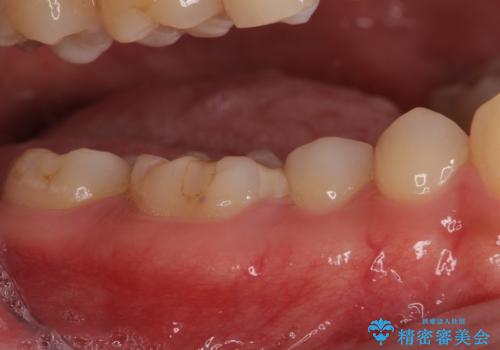

左上奥と右下奥に治療中の歯があり、虫歯を取っている途中で仮詰めの材料が充填されている状態でした。

仮詰め材を外すと虫歯が残っていたので、全てを取り除いた後に、ゴールドインレーの型どりを行いました。

ゴールドインレーをご自身で選択いただいたものの、どういった仕上がりとなるか不安を感じていたようですが、実際に装着された口腔内をご覧になり、思ったほど金属色が気にならないとのことでした。